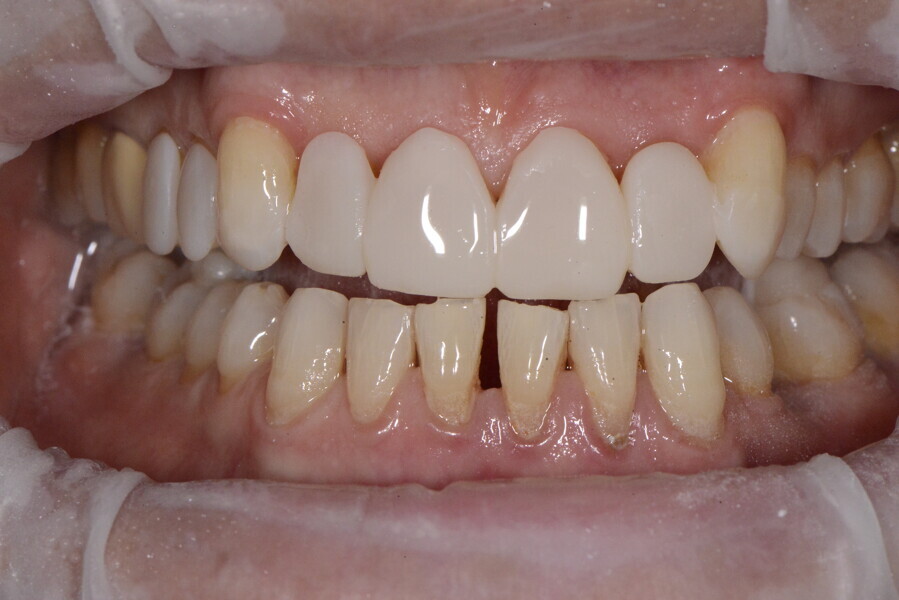

After the first phase of aligner treatment, we had achieved better inter-arch coherence, better maxillary arch expansion, and some space for improving the anterior tooth proportions restoratively (Fig. 19). We then temporarily restored the anterior teeth directly with composite, closing the spaces, improving the tooth proportions and further increasing the maxillary arch expansion (Fig. 20). We used restorative arch expansion to reduce the orthodontic destabilisation of the teeth to achieve the correct inter-arch coherence and retain the teeth in the cortical bone.38 A refinement aligner phase was undertaken to improve the final alignment of the gingival zenith and to improve the inter-arch coherence (Fig. 21). The periods of the first orthodontic phase and of the refinement were used to augment the mandibular and maxillary bone and to place the implants (Fig. 22). At the end of the orthodontic treatment, the case was finalised with ceramic veneers in the anterior area and temporary restorations on the implants in the posterior area (Figs. 23–26).

The provisional phase of about four months was important to allow the peri-implant tissue to mature and to teach the patient to chew correctly with chewing gum, cotton rolls and silicone masticatory sticks. This is fundamental training for the patient to achieve the correct alternating unilateral masticatory cycle needed to obtain the ideal rehabilitation of the masticatory system. We wanted the patient to achieve ideal masticatory and swallowing function. After sufficient rehabilitation time, we finalised the case with posterior zirconia crowns screwed on to the implants (Fig. 27).26